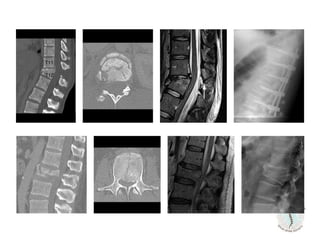

18 yr-old

MVA

Normal

neurological exam

63 yr-old

Fall from hight